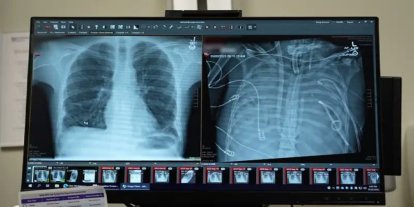

Hastanede gerçekleştirilen kontroller sırasında sol böbrekte kitle saptanmasının ardından hastaya ileri tetkikler uygulandı. Yapılan değerlendirmelerde kitlenin acil cerrahi müdahale gerektirdiği belirlendi.

Siirt Eğitim ve Araştırma Hastanesi Üroloji Kliniği Öğretim Üyesi Prof. Dr. Azmi Levent Sağnak ile Üroloji Uzmanı Op. Dr. Samir Jafarguliyev tarafından hastaya radikal nefrektomi ameliyatı uygulanmasına karar verildi.

“Sol böbrekte saptanan kitlenin boyutu ve yerleşimi nedeniyle radikal nefrektomi kararı aldık. Ameliyat, ekip çalışmasıyla planlandığı şekilde ve sorunsuz geçti. Erken tanı sayesinde hastamızın tedavi süreci başarılı bir şekilde tamamlandı.”